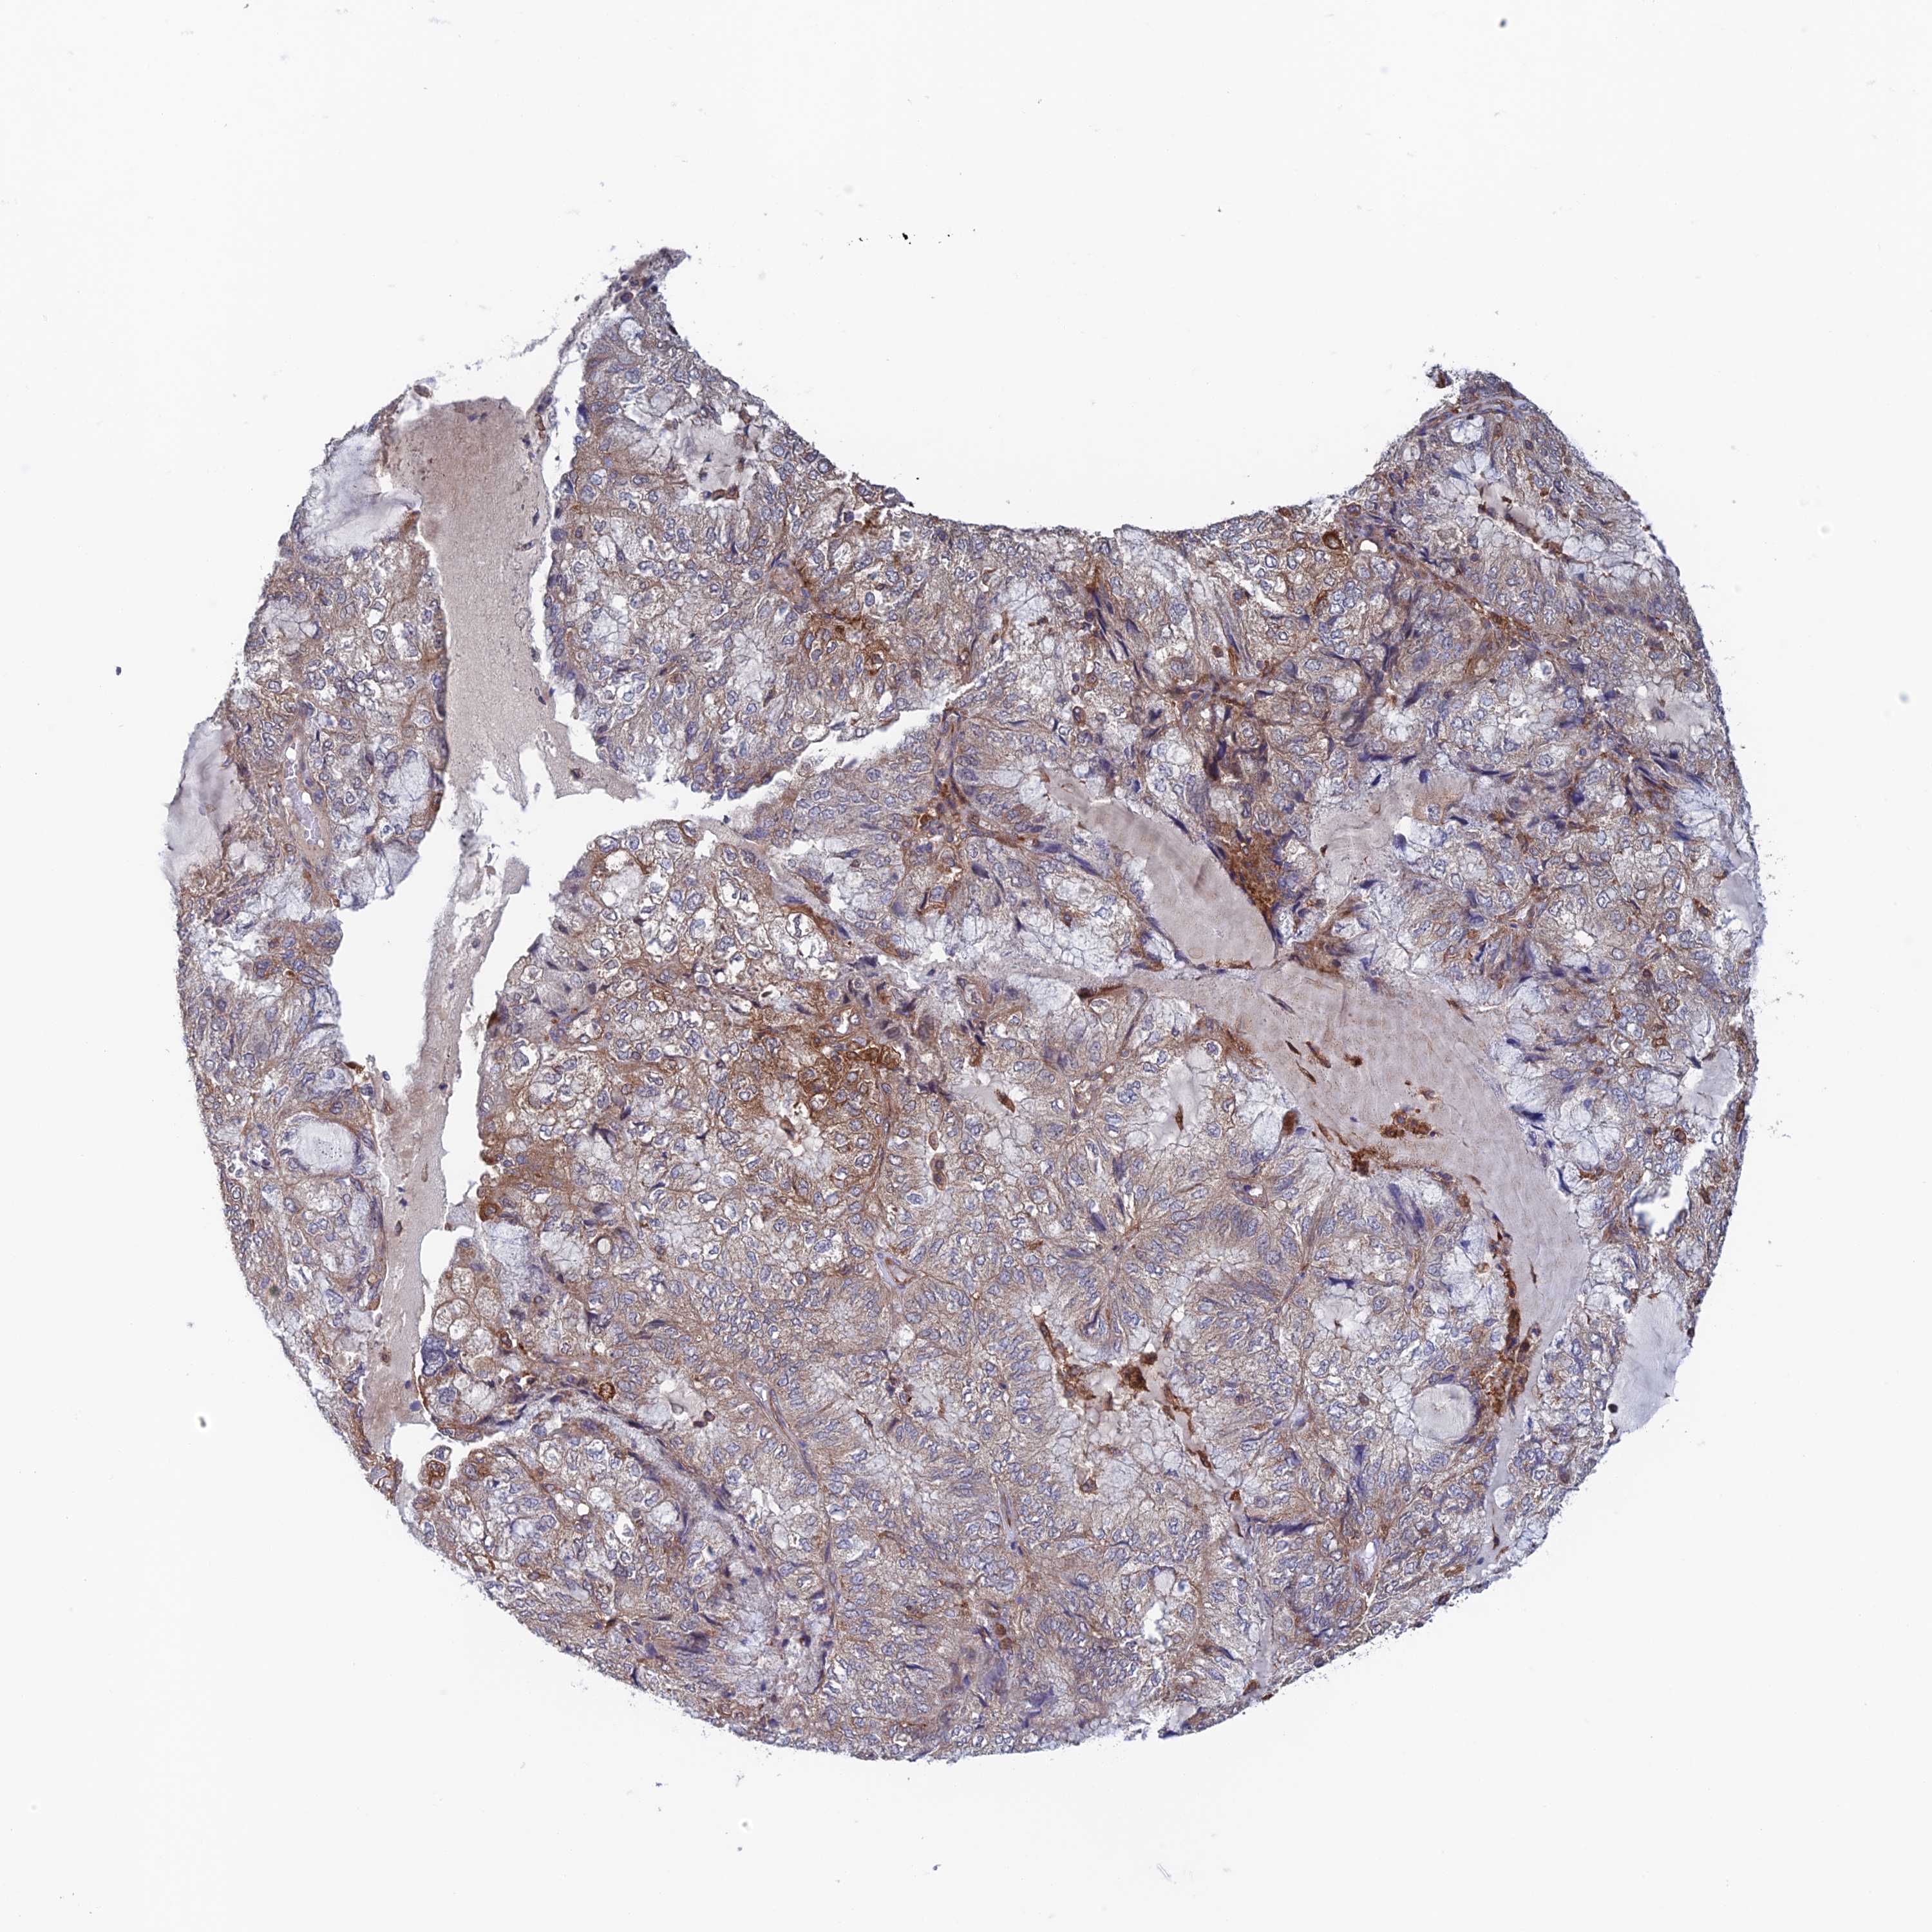

ENDOMETRIAL CANCER - Protein expressioni

A mouse-over function shows sample information and annotation data. Click on an image to view it in a full screen mode. Samples can be filtered based on level of antibody staining by selecting one or several of the following categories: high, medium, low and not detected. The assay and annotation is described here.

Note that samples used for immunohistochemistry by the Human Protein Atlas do not correspond to samples in the TCGA dataset.

Antibody stainingi

Antibody staining in the annotated cell types in the current human tissue is reported as not detected, low, medium, or high, based on conventional immunohistochemistry profiling in selected tissues. This score is based on the combination of the staining intensity and fraction of stained cells.

Each image is clickable and will lead to virtual microscopy that enables deeper exploration of all samples and also displays staining intensity scores, fraction scores and subcellular localization as well as patient and tissue information for each sample.

Antibody HPA044186

Antibody HPA063605

Staining

High

Medium

Low

Not detected

Intensity

Strong

Moderate

Weak

Negative

Quantity

>75%

75%-25%

<25%

None

Location

Nuclear

Cytoplasmic/membranous

Cytoplasmic/membranous,nuclear

Adenocarcinoma, NOS

Adenocarcinoma, metastatic, NOS